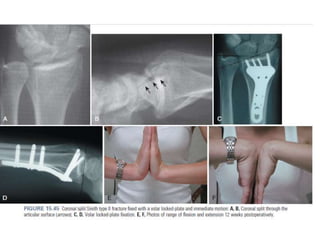

Reducción abierta placa volar

• Mínima conminución volar facilita la reducción de la dorsal

fracturas desplazadas.

• Facilita la restauración de longitud radial, inclinación e inclinación

volar.

•Preserva el suministro vascular de fragmentos dorsal conminuto.

• Debido a que el compartimento volar de la muñeca tiene una

sección transversal mayor espacio y el implante está separado del

flexor

tendones por el pronador cuadrado, la incidencia de flexores

las complicaciones del tendón se minimizan.

• El uso de diseños de placa voladora de ángulo fijo evita el "alternar"

del tornillo en el fragmento distal y por lo tanto reduce el peligro de

desplazamiento secundario